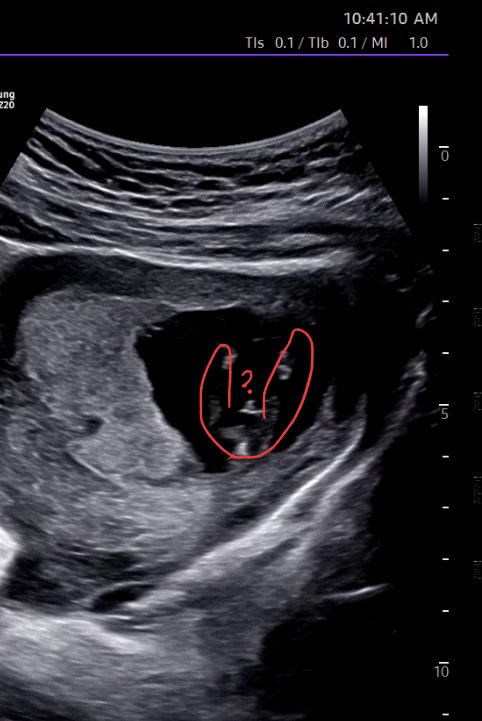

13주1일찬데 혹시 🌶️일까요..?

13주 다리사이에 뭔가 반짝이는데 고추같아보이시나요..?🤣

결과나왓어요 아들이래요 ㅎㅎㅎ